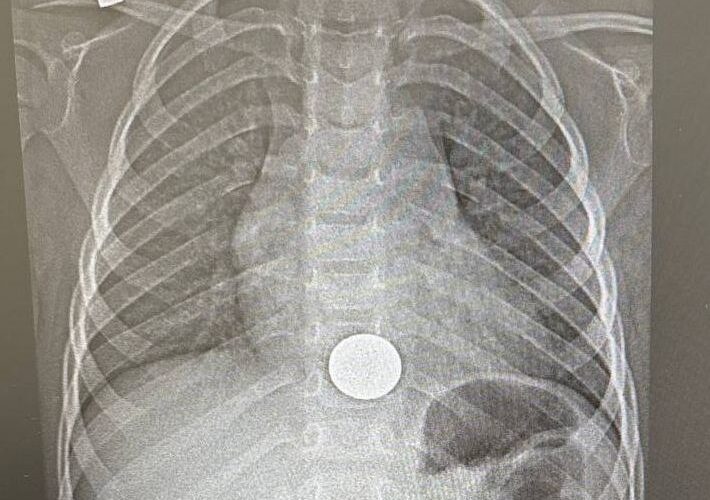

Малыш поступил в Нижнекамскую детскую районную больницу с жалобами на боли за грудиной. Как выяснилось, он взял монету у старшего брата поиграть и случайно проглотил её. Мама сразу отвезла сына в больницу, где рентген подтвердил: монета застряла в пищеводе.

Хирург с помощью эндоскопа удалил монету. После этого ребёнка перевели в хирургическое отделение, а на следующий день, убедившись, что его состояние в норме, выписали домой.